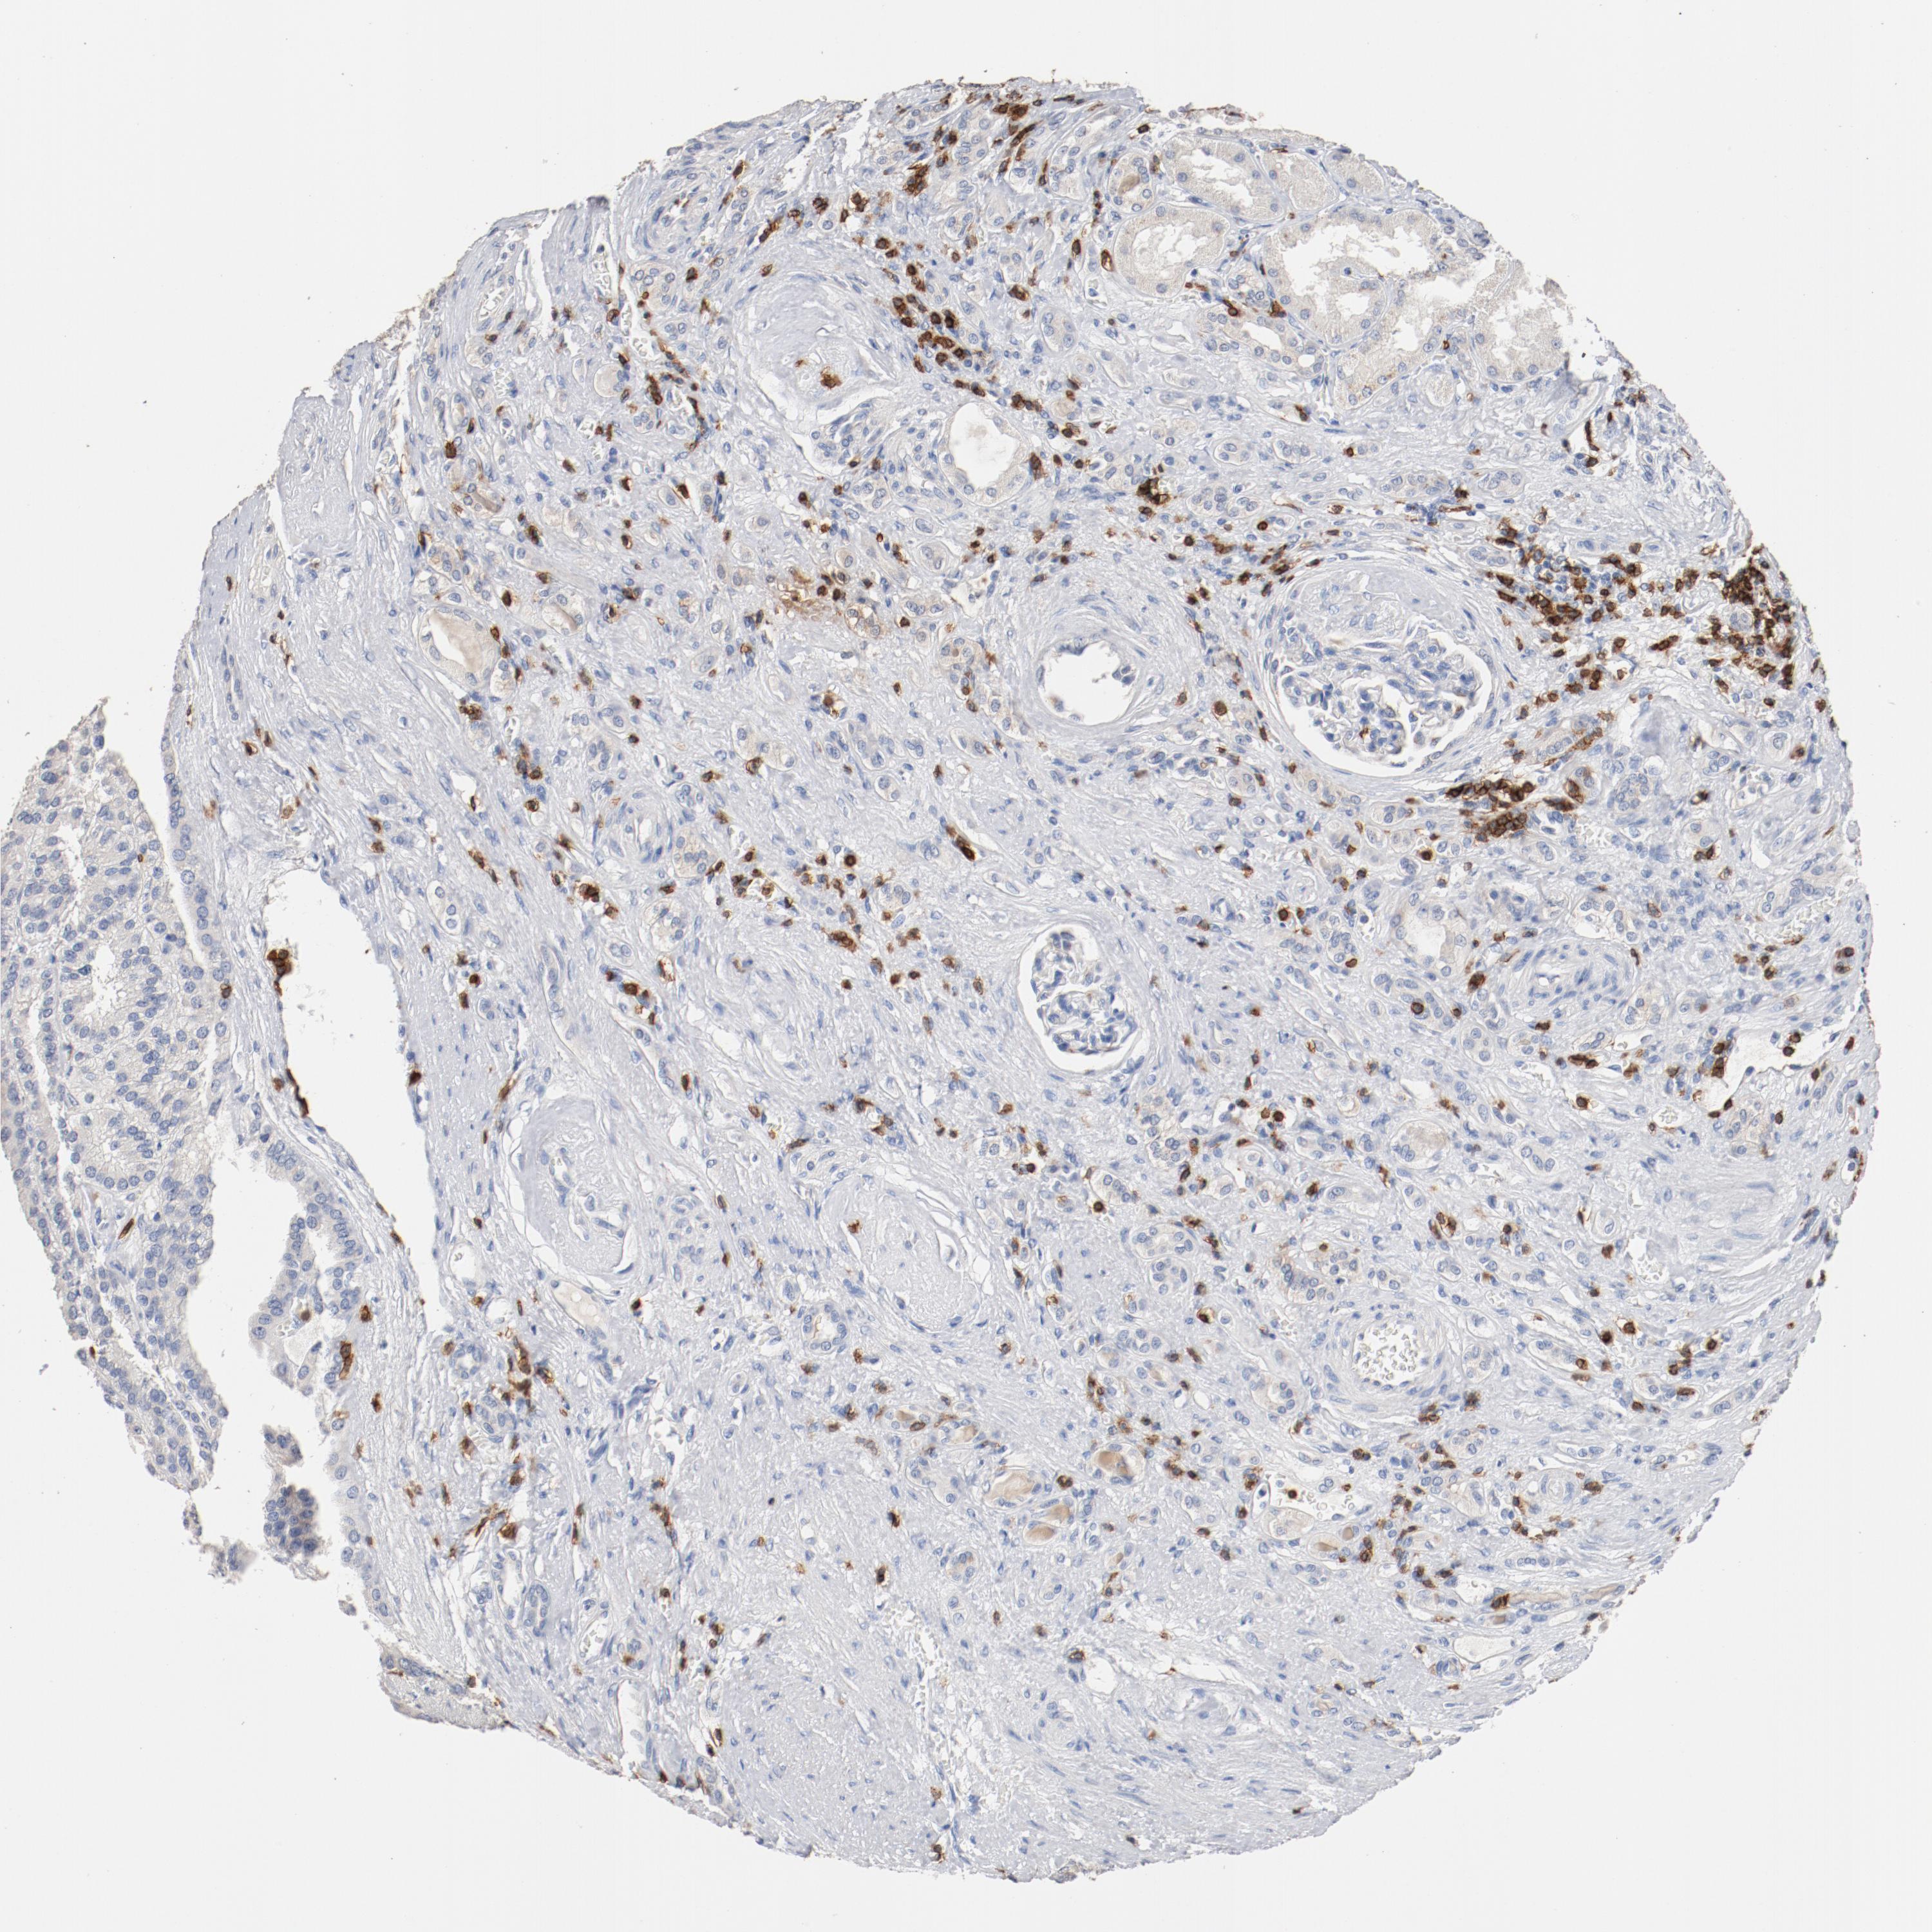

KIDNEY RENAL CLEAR CELL CARCINOMA (VALIDATION) - Interactive survival scatter ploti

The Survival Scatter plot shows the clinical status (i.e. dead or alive) for all individuals in the patient cohort, based on the same data that underlies the corresponding Kaplan-Meier plots. Patients that are alive at last time for follow-up are shown in blue and patients who have died during the study are shown in red.

The x-axis shows the expression levels (FPKM) of the investigated gene in the tumor tissue at the time of diagnosis. The y-axis shows the follow-up time after diagnosis (years). Both axes are complimented with kernel density curves demonstrating the data density over the axes. The top density plot shows the expression levels (FPKM) distribution among dead (red) and alive patients (blue). The right density plot shows the data density of the survived years of dead patients with high and low expression levels respectively, stratified using the cutoff indicated by the vertical dashed line through the Survival Scatter plot. This cutoff is automatically defined based on the FPKM cutoff that minimizes the p-score. The cutoff can be changed by dragging the vertical line or by entering a cutoff value in the square labeled "Current cut-off".

Under the Survival Scatter plot the p-score landscape (black curve; left axis) is shown together with dead median separation (red curve; right axis). Dead median separation is the difference in median mRNA expression between patients who have died with high and low expression, respectively. It is calculated as follows: median FPKM expression of dead patients with high expression - median FPKM expression of dead patients with low expression. This is intended to aid the user in visually exploring custom cutoffs and the associated p-scores and dead median separation.

Individual patient data is displayed and can be filtered by clicking on one or more of the category buttons on the top of the page. Categories describing expression level and patient information include: high, low, alive, dead, female, male and tumor stages. The scale of the x-axis can be toggled between linear and log-scale by clicking on the "x log" button. Mouse-over function shows TCGA ID, patient information and mRNA expression (FPKM) for each patient.

& Survival analysisi

Kaplan-Meier plots summarize results from analysis of correlation between mRNA expression level and patient survival. Patients were divided based on level of expression into one of the two groups "low" (under cut off) or "high" (over cut off). X-axis shows time for survival (years) and y-axis shows the probability of survival, where 1.0 corresponds to 100 percent.

CD247 is not prognostic in Kidney Renal Clear Cell Carcinoma (validation)

Best expression cut offi

Based on the FPKM value of each gene, patients were classified into two groups and association between prognosis (survival) and gene expression (FPKM) was examined. The best expression cut-off refers the FPKM value that yields maximal difference with regard to survival between the two groups at the lowest log-rank P-value. Best expression cut-off was selected based on survival analysis .

When clicking on this number, the vertical dashed line indicating cut-off, the interactive survival plot, and the Kaplan-Meier curve will be adjusted to show results based on the best expression cut-off.

: 14.81

P scorei

Log-rank P value for Kaplan-Meier plot showing results from analysis of correlation between mRNA expression level and patient survival.

N/A

TCGA RNA samplesi

RNA-seq data is reported as average FPKM (number Fragments Per Kilobase of exon per Million reads), generated by the The Cancer Genome Atlas (TCGA) .

Normal distribution across the dataset is visualized with box plots, shown as median and 25th and 75th percentiles. Points are displayed as outliers if they are above or below 1.5 times the interquartile range. FPKM values of the individual samples are presented next to the box plot.

Average pTPM 11.7

Number of samples 100